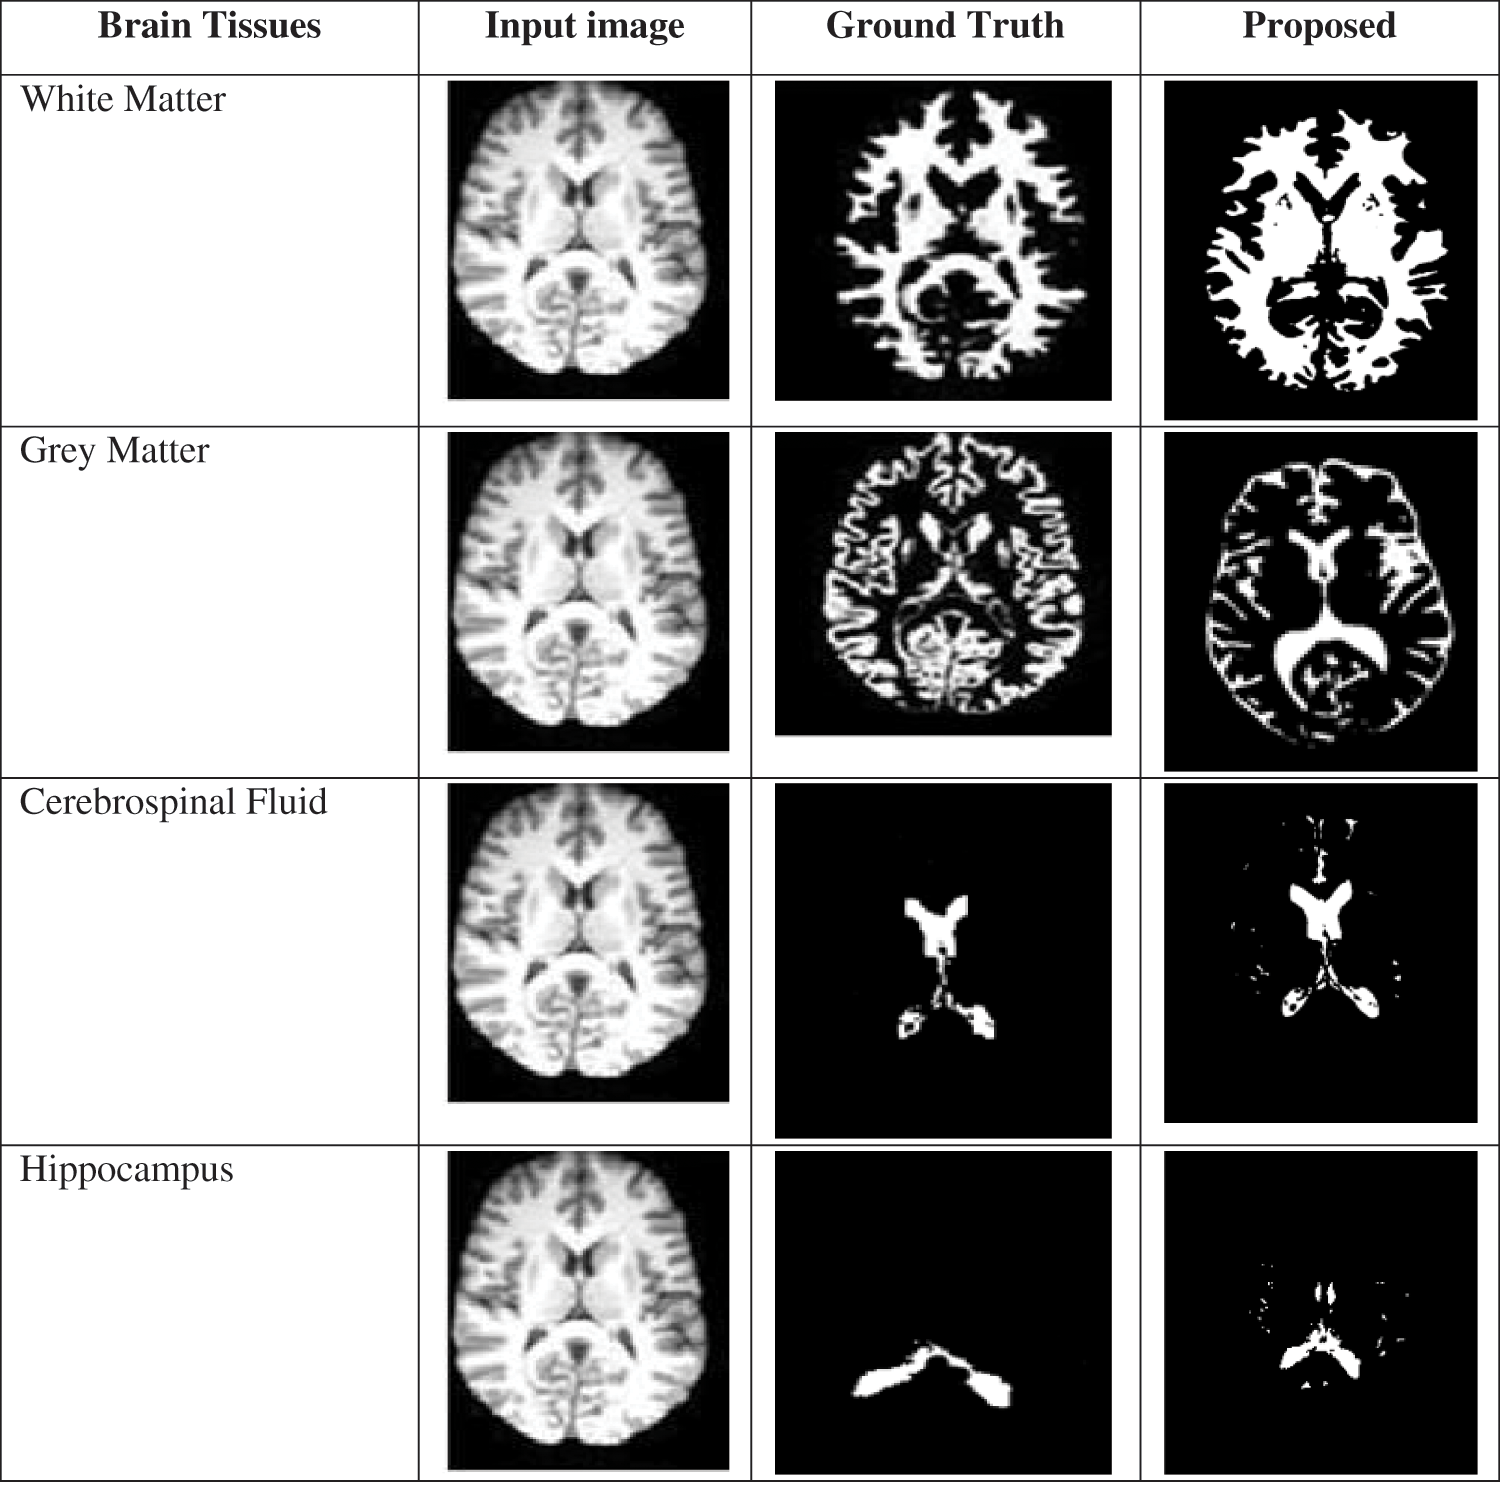

The segmented images of the brain tissues and the comparison among the ground truth images are given in Fig. 6. From the segmented images, it is revealed that the margins between the grey and white matter are much more distinct, bold, and contrast-enhancing. The hippocampus area boundary is additionally apparent. In conclusion, the suggested method shows that it is efficient at extracting meaningful edge points from brain MRI data. As a result, it is possible to identify the stages of Alzheimer’s disease with greater accuracy.

Figure 6: Comparison of a proposed segmented image with ground truth